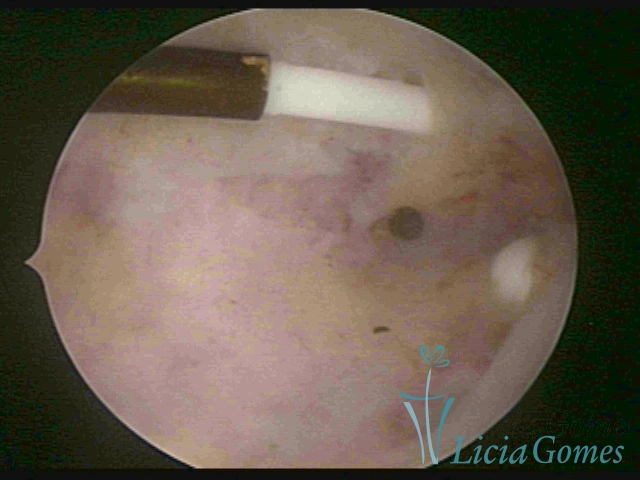

Cesarean section scar with a non-absorbed suture, as a foreign body

×